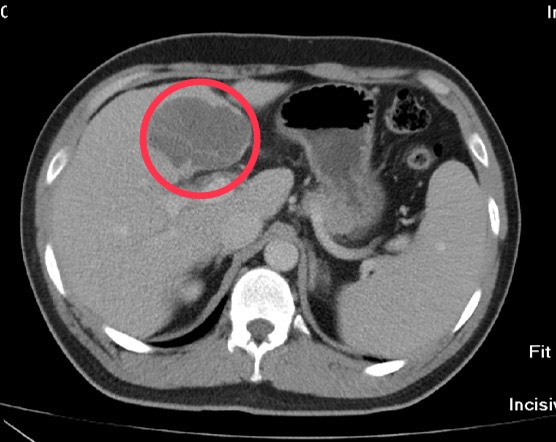

三十歲移工的華人姓氏為沈,他表示,當時身體落地後站不起來,下背非常疼痛必須有人攙扶。陳明慶醫師從X光片影像發現第十二節胸椎呈現明顯爆裂性骨折,進一步透過電腦斷層確定是脊椎骨折中嚴重的「屈曲牽張性骨折(chance fracture)」,立即為沈先生手術治療。